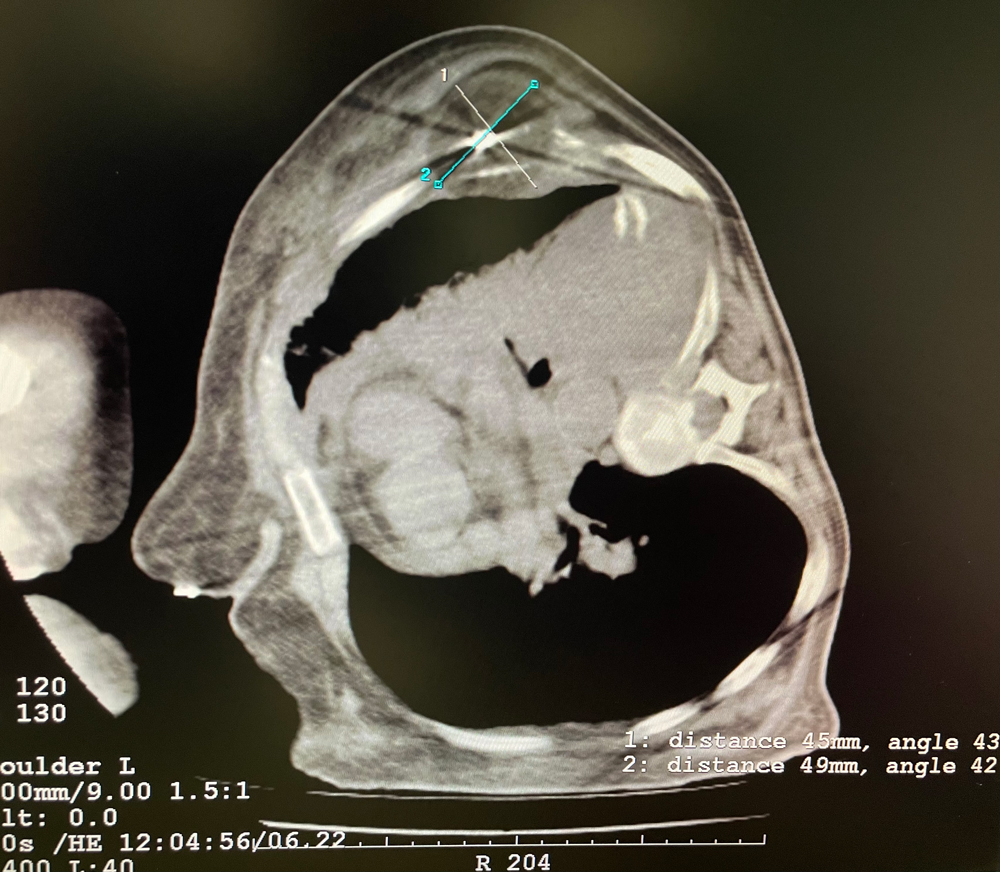

女,56岁,肺转移瘤,骶骨、左侧肋骨各一转移灶,病灶大小均为5cm。骶骨转移灶、肋骨转移灶各进行2个冻融循环。患者术后状况良好。

女,42岁,复发性脂肪瘤,病灶位于右侧膝关节,直径大小13cm。采用双针方案,共进行6个冻融循环,最大冰球直径达8.2cm,术中多方位治疗全面覆盖病灶范围。患者术后状况良好。